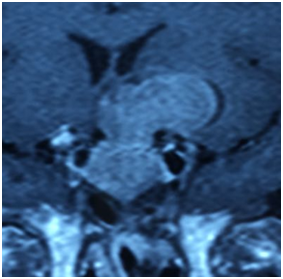

Subsequently a pituitary MRI (Figure1) was done; it showed a pituitary macro-adenoma, with a superior and left lateral extension. A CT-scan exam showed multiple secondary pulmonary localizations and a laboratory evaluation confirmed the hyper-secretion of the growth hormone (GH) with a value of 27. 20ng/ml (0.01 to 3.61). The same result was found for the dosage of IGF-1 estimated to 3906.5ng/ml when female’s (41-60 yr-old) normal value ranges between 43 and 267ng/ml.

Figure 1 Pituitary MRI showing pituitary macro‑adenoma, with a superior and left lateral extension.